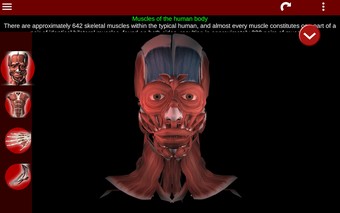

Esta herramienta educativa proporciona una descripción de cada músculo del cuerpo humano, así como un modelo tridimensional del sistema muscular. Con sólo tocar con el dedo, la aplicación revelará la información pertinente.

Los usuarios pueden hacer zoom sobre el músculo, así como elegir si ocultar o mostrar los datos. La orientación puede ser horizontal o vertical, según convenga más.